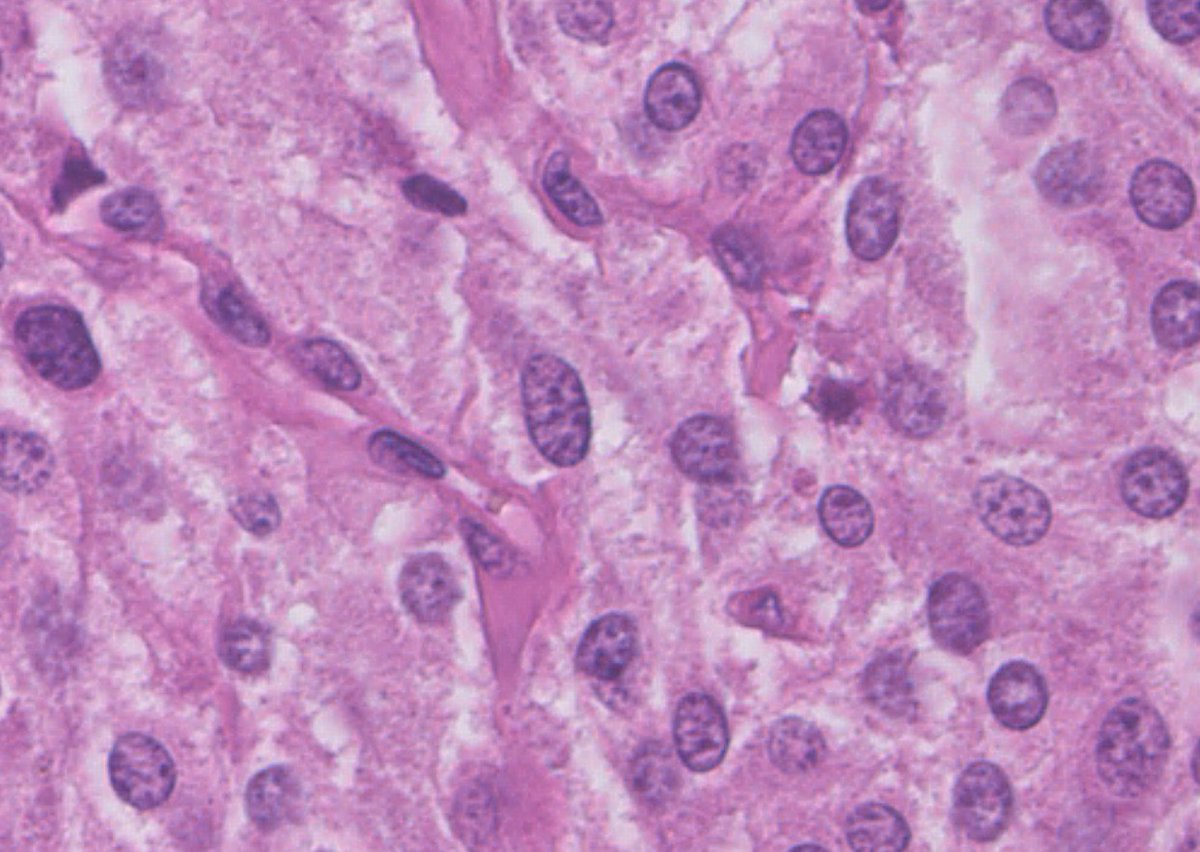

1/4 Dedicated to the memory of Dr Ondrej Hes x.com/GU_Path_Societ… Adult, medullary based kidney tumour - large discohesive polygonal, rhabdoid cells - multinucleated cells - cytoplasmic vacuoles #PathTwitter #PathResidents #Pathology #GUPath Ahmad Dhia GU Pathology Society (GUPS)